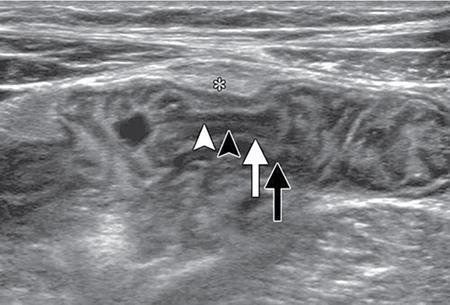

Ultrasonography (USG)

Kulbir Ahlawat, Ravi Chaudhary, Arvind Pandey, Anuj Bahl, Navni Garg, Sonam Shah, Sonali Sharma EMBRIOLOGY AND ANATOMY OF COLON Sonali Sharma A deep understanding of the development and the embryology of the colon is essential to understand the variety of the developmental anomalies related to the aberrations in the normal embryological processes (Table 8.4.1.1). Broadly the development of the colon can be summarized in three stages: The rate of growth of the embryo exceeds the growth rate of the yolk sac during the third and the fourth weeks of development. During the fifth week there is development of the omphalomesenteric duct or the Vitello intestinal duct or the yolk stalk which serves as a connection between the extraembryonic and the intraembryonic coelom (Fig. 8.4.1.1). The midgut at this point is divided into two equal length segments and the loop has its axis at the superior mesenteric artery (SMA). The apex is marked by the yolk stalk or the omphalomesenteric duct. There is a periarterial segment and the postarterial segment of the loop, the former starting at the foregut–midgut junction and ending at the apex. The postarterial segment lies between the apex and the midgut–hindgut junction. Eleventh week marks the beginning of the return of the postarterial segment of the gut, which continues to rotate in front and then to the right of the SMA. By the twelfth week the colon completes a 270-degree anticlockwise rotation with prior 90 degrees during herniation, and a further 180-degree counterclockwise rotation during the reduction of the postarterial segment. The prearterial segment gives rise to: Postpapillary duodenum, jejunum, ileum (major part) The postarterial segment gives rise to: Terminal ileum, caecum, appendix, ascending colon, transverse colon (major part) There is a switch over to the hind gut at the junction of the proximal two-thirds and the distal one-third of the transverse colon where there is also a switch over in the arteries supplying the segments, with SMA (middle colic) supplying the proximal segment and the inferior mesenteric artery (IMA, left colic) supplying the distal segment. The fifth week also marks the development of a small swelling in the proximal postarterial segment which represents the caecal bud. There is the herniation of the midgut at the sixth week of development called the physiological herniation of the gut. At this time there is growth of the liver, and the right lobe pushes the prearterial segment downwards and to the right. The series of events represent a 90-degree counterclockwise rotation when viewed enface (Fig. 8.4.1.2). The anomalies of this stage (stage of physiological herniation) are rare and include situs inversus, inverted duodenum and extroversion of the cloaca. With growth of the peritoneal cavity and no further significant growth of the liver, there develops a free space within the peritoneal cavity for the reduction of the midgut hernia at about the tenth week of development. Eleventh week marks the beginning of the return of the postarterial segment of the gut, which continues to rotate in front and then to the right of the SMA. By the twelfth week the colon completes a 270-degree anticlockwise rotation with prior 90 degrees during herniation, and a further 180-degree counterclockwise rotation during the reduction of the postarterial segment (Fig. 8.4.1.2). There occurs the fixation of the gut in this final sequence of events which start towards the later part of the first trimester. Anomalies of the reduction phase of the physiological hernia are relatively more common than the ones that originate from the stage of physiological hernia and include nonrotation, malrotation, reversed rotation, internal hernia and omphalocele (Fig. 8.4.1.3). There is a discrepancy in the growth rates of the base of the caecum and the apex of the caecum which leads to the formation of an appendage called the appendix. Further till the fifth month of gestation there is a progressive gradual resorption of the dorsal mesentery. Gradually, fusion of parts of the primitive mesentery occurs, with fixation of the duodenum, and the ascending and descending parts of the colon to the posterior abdominal wall in their final position. Anomalies of this stage of fixation are common and include mobile caecum, subhepatic or undescended caecum, hyperdescent of the caecum and persistent colonic mesentery (Fig. 8.4.1.3). The mesentery of the transverse colon (mesocolon) persists with its partial fusion with the greater omentum leading to the formation of the gastrocolic ligament. The distal end of the transverse mesocolon condenses to form the phrenicocolic ligament, which suspends the transverse colon near the splenic flexure fixing it to the diaphragm in the left upper abdomen. It also prevents the spread of pathologies from the left paracolic gutters to the left upper abdomen. The sigmoid colon continues to maintain it dorsal mesentery or sigmoid mesocolon at its posterior aspect. The length of the mesentery is short relative to the variable length (sometimes very long) of the colon to which it is attached. This discrepancy leads to the sigmoid volvulus. Colon is formed from the midgut and the hind gut with the junction of the proximal two-thirds and distal one-third of the transverse colon being the point of demarcation between the two. The midgut development continues beyond the opening of the papilla, to form the duodenum beyond the papilla, ascending colon and the proximal two-thirds of the transverse colon. This segment is supplied by the Superior Mesenteric Artery with corresponding venous and lymphatic drainage (Fig. 8.4.1.4). The distal third of the transverse colon, descending colon, sigmoid colon, rectum and the anal canal above the dentate line all are derived from the hind gut and supplied by the Inferior Mesenteric Artery with corresponding venous drainage and lymphatics (Fig. 8.4.1.3). Enteric nervous system (ENS) functions independent of the CNS and is thus referred to as the ‘Second Brain’ and it regulates many aspects of gastrointestinal physiology including peristalsis, sphincter tone, glandular secretions, smooth muscle activity and microcirculation. The neuroenteric ganglion cells migrate from the neural crest to the upper end of the alimentary tract and then follow vagal fibres caudad during the first trimester. The ENS is composed of two types of ganglionated plexuses: the Auerbach (myenteric) plexus, which is located in the outer muscular layer and regulates gastrointestinal tract motility and function of extraluminal organs, and the Meissner (submucosal) plexus, which regulates enteral secretory activity. In contrast to the neural crest-derived cells of the enteric plexuses, interstitial cells of Cajal (ICCS), which serve as the ‘pacemakers of the intestine’, arise from intestinal mesenchyme. Sympathetic innervation: L2–L5 roots, inferior and superior mesenteric plexus and coeliac ganglia. Parasympathetic innervation: The Vagus nerve and sacral spinal cord (S2–S4 spinal nerves). Great details of the various disorders are beyond the scope of this book. A short review is written (Table 8.4.1.2). Duodenal atresia (11%) – most common Meckel’s diverticulum (11%) – second commonest Omphalocele (9%) Other stenosis or atresia (5%) Hirschsprung’s disease (2%). Cardiac and orthopaedic anomalies Biliary atresia Pancreatic anomalies Microcolon Esophageal webs Tracheoesophageal fistula It is commonly known as malrotation and occurs due to an arrest of the first 90 degrees rotation of the midgut which causes the prearterial segment to lie to the right of the hernial sac and SMA and the postarterial segment to the left. The dorsal mesentery lies in the midline and is shared by both the pre and the postarterial segments. This makes the bowel loops imbalanced and mobile and prone to volvulus. The twisting of the midgut loop can occur mostly at the level of the duodenojejunal junction and less commonly at the level of the midtransverse colon. There is a disruption of the normal SMA to SMV relationship, with the SMV seen to the left of the SMA in this pathology. In this there is a reversal of the sequence of return of the midgut with postarterial segment returning first and lying posterior to the SMA with the duodenum and the small bowel lying anterior to the colon. Abnormal mesenteric bands may form leading to obstruction. Failure of the midgut to retract into the abdominal cavity with retention in the hernial sac. The colon may fail to complete its final 180-degree rotation and lie in the right upper quadrant. Incomplete resorption of the mesentery may lead to abnormally mobile colon segments due to centrally placed dorsal mesentery. It is interesting to know that the rotation anomaly of the prearterial segment may be an isolated entity but, the rotation anomaly of the postarterial segment is invariably associated with the anomaly of the prearterial segment. Caecum is an intraperitoneal organ either almost completely invested with peritoneum or at least invested by it in its lower half. It is fixed by a small mesocaecum. In 5% individuals the caecum rests directly on the iliacus muscle and the psoas major muscle due to lack of the peritoneum. Also, an abnormally mobile caecum and ascending colon may be seen in about 10%–22% individuals usually due to a long mesentery. Thus varied locations of the caecum may be seen. This is a fixation anomaly and may lead to a volvulus. This exclusively affects the postarterial segment with normal mobility and position of the prearterial segment. The caecum may lie in the left upper quadrant. Errors in the resorption of the dorsal mesentry, may lead to development of abnormal fossae through which the loops of the bowel may herniate (Fig. 8.4.1.5). Few common ones are detailed below: It formed the incomplete fusion of the mesentry of the descending colon. The bowel loops may herniate under the colon and in front of the IMA. This leads to the left paraduodenal internal hernia. A defect in the small bowel mesentery leads to herniation of the loops in the left upper quadrant, beneath the SMA to the right. This is called the right preduodenal hernia and is less common the left preduodenal hernia. Work on the anatomy of the colon dates back to the 16th century with the pioneering work of Andreas Vesalius. The versatile and ever evolving radiological procedures have further added to this knowledge over the past few decades, improving our understanding of this organ. There are no two opinions on the vital functions of absorption of nutrients, water and electrolytes and transmission and storage of residue performed by this organ. The colon is a long tubular conduit with variable length in different individuals, measuring approximately 120–200 cm (Table 8.4.1.3). Large bowel is differentiated from the small intestine structurally due to its unique longitudinal muscular bands called taenia and characteristic macroscopic saccular appearance and haustral pattern and Appendices Epiploic (Fig. 8.4.1.6). The saccular appearance is attributed to the shorter length of the longitudinal muscle fibre bands or taenia, which are about one-sixth shorter in length than the length of the colon per se. Also the haustral pattern or segmented appearance seen in the colon is characteristic, wherein the haustra are separated by the semilunar cresentric incomplete folds known as plicae semilunaris which may be better visualized when appropriate colonic distension is obtained by barium or air insufflation. The colon also has circumferential folds extending around the luminal surface called the plicae circularis, also seen in the small intestine where they represent folds of the mucus membrane. Thus, the plicae circularis are not exclusive to the colon. The longitudinal muscle bands called the taenia coli run along the serosal surface of the colon, and arrange into three muscle bands namely taenia liberis, taenia omentalis and taenia mesocolica, that are located 120 degrees from each other, and run from the caecum to proximal rectum. Taenia omentalis runs posterolaterally and is attached to greater omentum, taenia mesocolica runs posteromedially and is attached to mesocolic taenia and taenia liberis is boundless and runs anteriorly. At the rectosigmoid junction, taenia expands to cover the rectum. At the level of the sacral promontry there is gradual transition between the colon and the rectum, with confluent muscle fibres giving the rectum a Taenia Free appearance. It is worthwhile here to mention briefly the Appendice epiploicae which are exclusive to the colon and not seen in the small intestine as well as rectum and beyond. These are fatty appendages which perform the fat storage reserve function and are located along the serosal surface of the colon. Inflammation of these is now a disclosed entity frequently encountered in the radiological practice. The colon is divided into the caecum including the vermiform appendix, ascending colon, transverse colon, descending colon and the sigmoid colon (Fig. 8.4.1.7). The ascending colon and the descending colon are retroperitoneal, while the caecum, transverse colon and the sigmoid colon are intraperitoneal. The caecum is the widest part of the colon measuring 7.5 cm in diameter while the sigmoid colon is the narrowest part measuring 2.5 cm. It is due to this reason that the caecal masses acquire a very large size before causing obstructive symptoms and present later in the course of disease while the sigmoid colon masses present earlier in the course of the disease with obstructive symptoms. At the posteromedial aspect of the caecal wall two elliptical folds form the orifice for the ileocaecal valve which is formed by the circular muscle layers of terminal ileum and has a typical nipple like appearance. Some authors have suggested that an intact ileocaecal valve is advantageous in patients of short bowel syndrome by increasing the absorption of the nutrients. The ileocaecal valve appears mostly incompetent on the Barium Enema. However, a competent valve is known to prevent colonic decompression in patients of high-grade colonic obstruction. The Vermiform Appendix is a blind-ended tubular appendage arising from the caecal wall at its base posteromedially. It lies mostly intraperitoneally (95%). It is more commonly directed medially towards the ileum, retro caecally or alternatively in the lesser pelvis. Apart from these commonest locations, the appendix may be subcaecal (31%), transverse retrocaecal (2%), paracaecal, preileal (1%) and ascending paracaecal retroileal/postileal (0.5%). Appendix lacks taeniae, haustra, plicae semilunaris and appendices epiploicae and is located at the site of confluence of the three taenia. The appendix can be variable in length ranging 2–20 cm. It is interesting to note that clinically an intraperitoneal appendix is more symptomatic due to inflammation of the parietal peritoneum as opposed to a retrocaecal appendix. The ascending colon is short measures 10–20 cm and lies within the anterior pararenal space. The ascending colon is a (secondarily) retroperitoneal structure covered only on its ventral and lateral surfaces by the posterior peritoneum, with the mesocolon fused with the retroperitoneum. The ascending mesocolon is not a real mesentery because it is not formed by two peritoneal layers suspending the colon. The ascending mesocolon follows the course of the ileocolic vessels and marginal vessels along the mesocolic side of the colon. As the ascending colon reaches the liver, it turns 90 degrees at the curve called the hepatic flexure to continue across the upper abdomen to the left side to form the transverse colon up to the spleen where it curves to form the splenic flexure. The colon is completely wrapped by the peritoneum at the site of junction of the hepatic flexure and the transverse colon. Transverse colon is the longest part of the colon measuring about 40–50 cm in length. Transverse colon is the most mobile part of the colon due to its well-developed mesentery and may even reach up to the pelvis. It is attached to the diaphragm by the phrenicocolic ligament. Transverse colon is an intraperitoneal segment of the colon. The greater omentum is fused to the taenia mesolica at the inferior surface of the transverse colon. Beyond the splenic flexure the colon turns inferiorly to continue as the descending colon which is (secondarily) retroperitoneal, immobile and measures approximately 25–45 cm. The descending colon reaches the left iliac fossa where it continues as the S-shaped sigmoid colon which has the caudal end at the level of S3 vertebra. The sigmoid colon is attached to the pelvis by the sigmoid mesocolon and is completely invested by the peritoneum. The sigmoid mesocolon has long length and is tortuous and these features make the sigmoid colon prone to volvulus. The sweep of the sigmoid colon into the pelvis can range from gentle to an omega loop to a redundant coiled appearance. These variations and looping tendency in the sigmoid colon make it a difficult part to evaluate at colonoscopy. It is an interesting fact the rectosigmoid region acts as a functional sphincter due to sharp angulation in this region along with narrow luminal diameter thereby increasing the transit of residue across this region and thereby increasing the intrasigmoid pressure making it prone to diverticulosis. The colon is supplied by the SMA and the IMA which are branches of the abdominal aorta. The SMA gives rise to 12–20 jejunal and ileal branches and then continuing as the ileocolic trunk shifting further to the right towards the caecum. The ileocolic artery is a relatively constant artery with not many variations in the course. The SMA gives rise to the right colic artery (RCA) and the middle colic artery (MCA) which may show variations (Fig. 8.4.1.8). The IMA bifurcates into an ascending branch and a descending branch. The descending branch runs caudally and supplies the descending colon (Fig. 8.4.1.9). In the pelvis it gives 2–6 sigmoidal arteries and becomes the superior haemorrhoidal artery also called the superior rectal artery. The anterior branch ascends and contributes to the formation of the Arc of Roilan. It is interesting to know that while most of the blood supply off the colon is segmental, the sigmoidal arteries form an arcade that is similar to the small bowel vasculature and have multiple anastomosis. It corresponds to the arteries. The marginal artery of Drummond is called the central anastomotic artery, runs along the entire medial aspect of the colon and provides the collateral circulation between the SMA and the IMA. A watershed zone called the Griffiths Critical Zone is seen at the junction of the proximal two-thirds and the distal one-third of the transverse colon which is the site between the blood supply by the SMA and the IMA branches is also the site where the midgut joins the hind gut. Another area of diminished blood supply is called the Sudeck’s point which is located near the rectosigmoid Junction. It is a point of anastomosis between the IMA and the internal iliac artery. There is another thick meandering artery called the Arc of Riolan that plays a critical role in providing collateral circulation between middle colic artery and the ascending branch of the left colic artery when either the SMA or IMA is occluded. The vasa recta supply the colonic lumen. The colon has a rich lymphatic supply, typically divided into: The sympathetic supply of the right colon originates from lower thoracic segments. They synapse with preaortic, coeliac and superior mesenteric ganglia. Parasympathetic supply is from the right Vagus nerve branch and the coeliac plexus. The sympathetic nerves supplying the left colon and rectum arise from L1 to L3. The large intestine measures about 60 cm in length. The muscularis is very poorly developed. The ascending and descending colon are relatively shorter than the transverse colon. The normal haustra and appendices epiploic are not present, giving the paediatric colon a very smooth outline. The haustra appear over the first 6 months of birth. IMAGING TECHNIQUES FOR COLON Navni Garg, Ravi Chaudhary Plain abdominal radiograph is usually the first imaging investigation requested in patients suspected of bowel obstruction and/or perforation. They aid in differentiating small bowel obstruction from large bowel obstruction (LBO). Specific signs on a plain radiograph prompt the radiologist towards considering particular aetiology. Various indications of abdominal radiograph are enlisted in Table 8.4.2.1. The abdominal radiography usually involves a supine radiograph (anteroposterior projection) and should include the diaphragm superiorly and ischial tuberosities inferiorly. An additional horizontal beam (upright, decubitus, or cross-table lateral) projection may be done where obstruction/perforation is suspected to detect small amounts of pneumoperitoneum and evaluate air–fluid levels. Some institutions prefer to perform an upright chest radiograph to detect small amount of intraperitoneal free gas. Horizontal beam radiographs should always be performed after placing the patient in upright or decubitus position for at least 5 minutes before exposing the radiograph. The size of the film or image receptor varies with the size of the patient. In adults, a 14 × 17 inch film is usually appropriate. Radiographs are usually taken at end expiration, wherever possible using low kVp (60–75 kVp). However, technical parameters are usually varied according to patient size. Few of the important indications are discussed here: Adynamic ileus is generalized dilatation of small and large bowel loops and is different from pseudo-obstruction as there are no chances of perforation in ileus. Frank distension of rectum implies ileus. Air–fluid levels not seen in pseudo-obstruction or ileus and favour obstruction. It is important to rationalize the use of radiographs and perform alternative radiation free modality like ultrasound wherever possible. USG is often the first modality used for imaging patients with abdominal pain. It is an inexpensive and widely available modality for abdominal imaging. However, limitations such as operator experience, patient’s body habitus, bowel gas–related artefacts and patient cooperation preclude the wide use of this noninvasive modality for imaging of colonic pathologies. Destruction of gut signature is harbinger of some malignant process, more so if length of bowel involved is short. However, aggressive inflammatory processes may also cause focal disruption of gut. Normally diseased bowel segment is better appreciated on USG due to reduced motility and thickened walls are larger and easier to see. Further, colour Doppler can be used to assess mural vascularity however due to low blood flow in the mural vessels and artefacts due to peristalsis, it may not always be possible to document hyper- or hypovascularity. Mural hypervascularity is usually seen in inflammatory or infectious diseases whereas hypovascularity in thickened bowel is suspicious of ischaemia. The guidelines of the European Federation of Societies for Ultrasound in Medicine and Biology have specified indications for the use of CEUS in IBD cases: Limitation of CEUS is bowel motility which leads to suboptimal imaging quality and only limited segment is evaluated at a time. Though CT is more reliable imaging modality in patients with diverticulitis, USG is helpful in early, uncomplicated diverticulitis especially in lean patients. Even with the advent of advanced imaging techniques, contrast enema continues to provide relevant information to clinicians and surgeons. The aim is to obtain good-quality images with various projections and least radiation exposure. Various indications and contraindications of contrast enema are enlisted in Table 8.4.2.2. Patient is advised to consume low-residue diet for previous 2 days and laxative a day before the examination. In our centre, two scout views are taken before contrast administration: AP abdomen and left lateral pelvis to check for adequate bowel preparation and rule out any obstruction/perforation. This is followed by introduction of a rectal tube lubricated with lidocaine jelly through the anal opening, taped to the sides and connected to an enema bag hanged on an IV pole. Either barium or water-soluble contrast can be used. Water-soluble contrast is used in patients with suspected colonic obstruction or volvulus, early postsurgical patients where perforation/leak is suspected or where Blind-ending colonic segments (e.g. rectal remnant following the Hartmann procedure or J-pouch) are present. It is also recommended in patients with distal intestinal obstruction syndrome/meconium ileus equivalent in patients with cystic fibrosis to demonstrate the level of the obstruction and possibly be therapeutic. Repeat enemas with water-soluble contrast agents over several days may be required to mobilize the tenacious stool plugs. Water-soluble contrast contains 300–370 mg of iodine/mL, equivalent to 60%–76% density. It may be diluted with water to 20%–30%, depending on the indication. For visualization of water-soluble contrast, kilovoltage of 70–80 kVp should be used during image acquisition. Contrast enema can be performed as single contrast or double contrast study. Single contrast study allows real-time imaging of colonic leaks and fistulas in inflammatory bowel diseases (IBDs) and postoperative patients whereas double contrast study provides better mucosal information in patients with failed colonoscopy for screening of colorectal malignancy. Single contrast study involves use of 20% w/v of barium. A kilovoltage of 100 kVp or greater should be used (depending on patient size) during image acquisition. Barium is allowed to flow and patient is turned to facilitate the passage of barium till it reaches the caecum and the ileocaecal valve (and possibly the appendix). Spot radiographs are taken intermittently to demonstrate each loop of colon with adequate barium coating and distension (Figs. 8.4.2.10–8.4.2.13). Manual or mechanical compression should be applied as appropriate to all accessible segments of the colon during fluoroscopy. Images should include (ACR Guidelines):